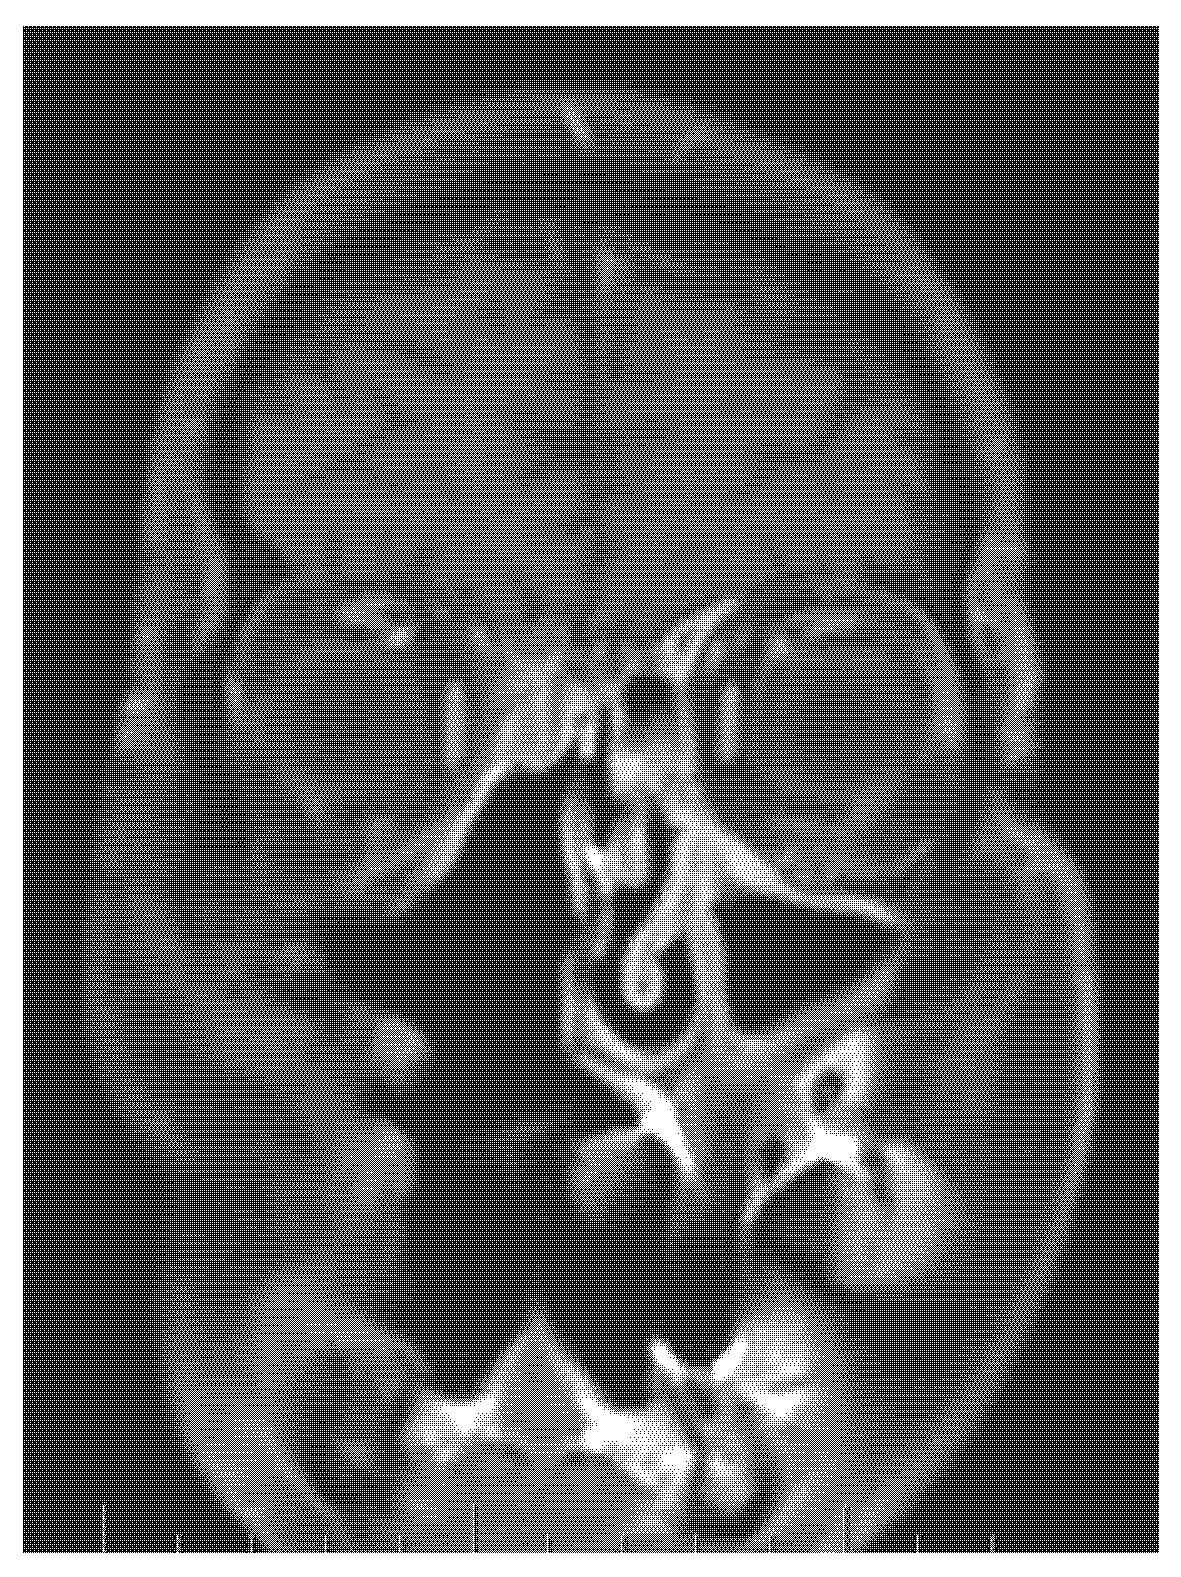

- CT, MRI scan (size, spread, and metastases of tumour mass), if necessary, PET scan, and USG.